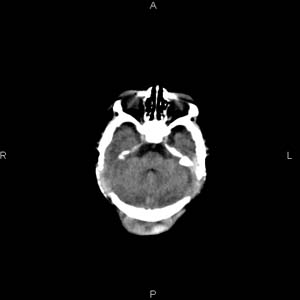

患者男,27天,出生后正常,今天中午在母亲怀里抱着吃奶在放下睡觉时发现后枕部慢慢出现一包块,来查头颅ct。无外伤史。包块内ct值47-51hu。请大家讨论。

支持脑膜脑膨出,双侧侧脑室三角区周围脑白质对称性低密度影,考虑缺血缺氧性脑病或肾上腺性脑白质营养不良。

\"中午在母亲怀里抱着吃奶在放下睡觉时发现后枕部慢慢出现一包块,包块内ct值47-51hu。

颅骨无缺损,骨缝无增宽.支持头皮血肿(血管破裂)